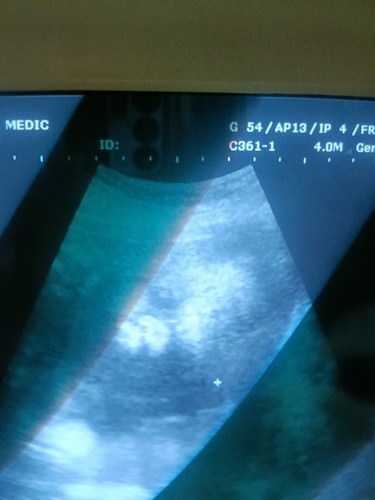

ไปอุนตร้าซาวมาแล้วค่ะลูกสาวแม่ 29สัปดาห์ วัดจากตัว แต่นับจากปจด27+6 แข็งเเรง ดิ้นเก่ง 1.4กก.

ลูกสาวแม่ท้อง2ด็ยังตื่นเต้นและรักมาก จะดูแลหนูให้ดีที่สุด